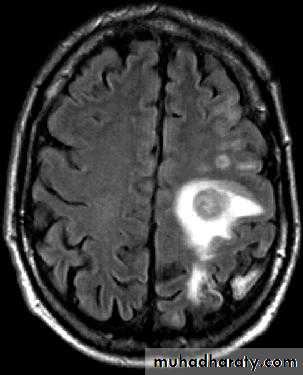

Brain Abscess MRI

• MRI is done with gadolinium enhancement.

• They will show a single (or multiple) space occupying lesion that is well delineated with an enhancing wall, with variable surrounding oedema.

• B. Radiological Investigations:• The differential diagnosis of a single brain abscess in CT or MRI is a solitary metastasis, primary brain tumour or cerebral infarction.

• The differential diagnosis of multiple brain abscesses is from multiple metastasis and tuberculoma.